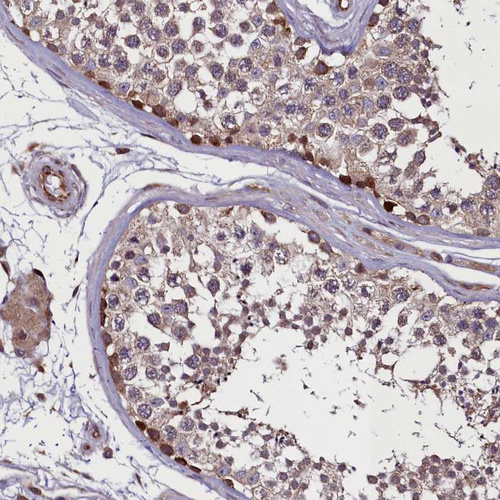

Immunohistochemical staining of human testis shows strong cytoplasmic positivity in spermatogonia.